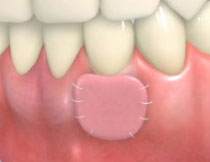

組織付着療法![]() |

![]() |

|

| 歯周病が進行したケースでは盲目下でポケット内の歯石を確実に除去するには限界があります。 | 局所麻酔をした後、歯茎を切開し、明視下にて歯根面の歯石や炎症組織を取り除き、歯周ポケットの除去をおこないました。 |